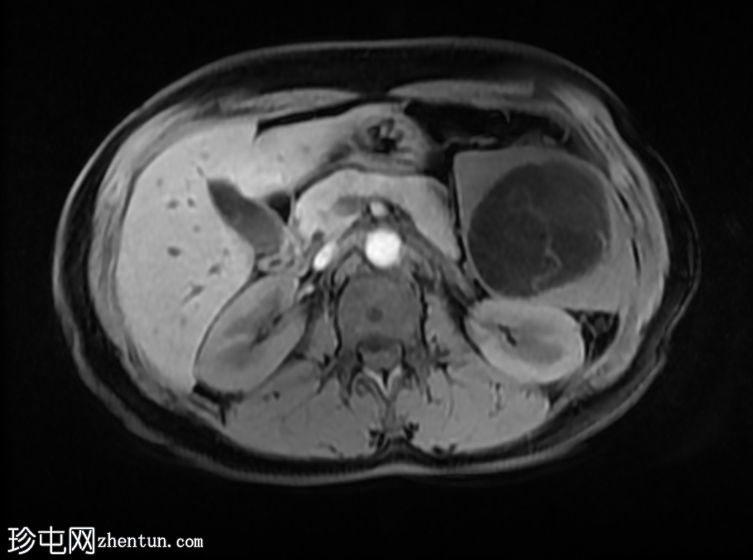

轴位

T2加权像

肝脏肿大,可见多发性双叶肝囊肿。

脾脏肿大,可见多发性大囊肿,内层脱离。

肝脾包虫囊肿的典型

影像

学表现。